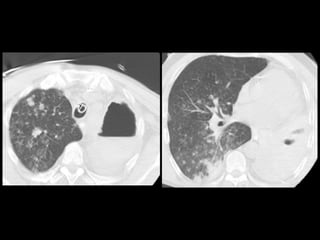

Mujer de 18 años con episodio de hemoptisis con

exploración ORL normal

Mujer de 18años con episodio de hemoptisis con exploración ORL normal